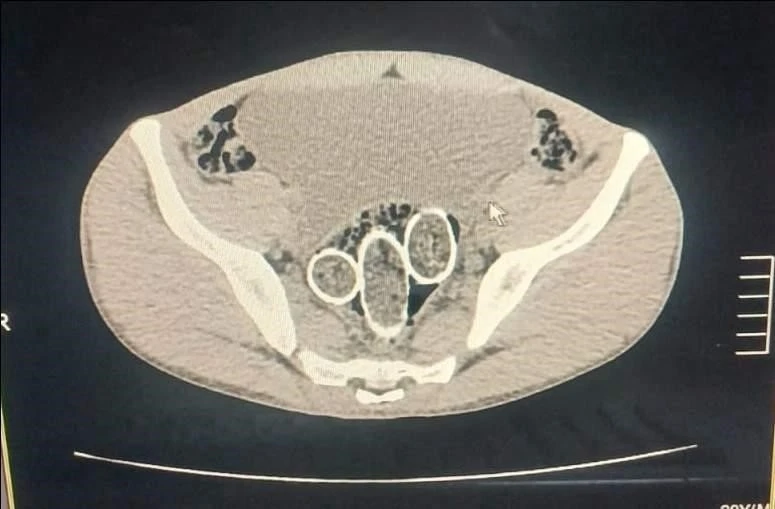

Denizli’de polisin düzenlediği uyuşturucu operasyonunda gözaltına alınan 5 şüpheliden 2’sinin yapılan iç beden muayenesinde rahim ve mideye saklanmış 320 gram uyuşturucu madde ele geçirildi.

Denizli İl Emniyet Müdürlüğü Narkotik Suçlarla Mücadele Şube Müdürlüğü ekiplerince, uyuşturucu ticaret yapan şahıs veya organizasyonların yakalanmasına yönelik operasyon düzenlendi. Düzenlenen eş zamanlı operasyonlarda 5 şüpheli şahıs yakalanırken, iki şahsın yaptırılan iç beden muayenesinde ve kullandıkları iki araçta yapılan incelemelerde rahimde ve midede uyuşturucu madde tespit edildi.